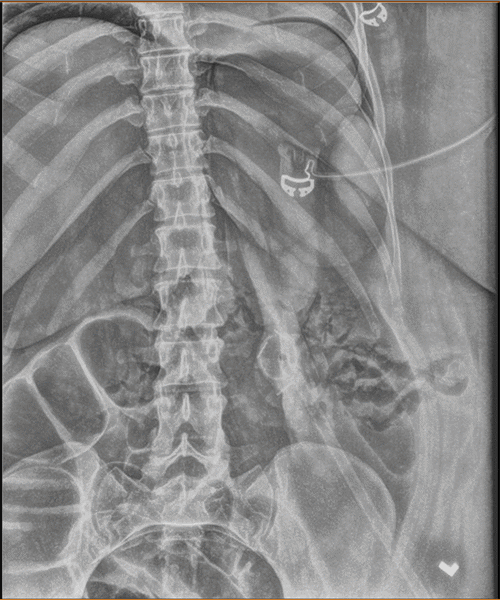

Within 30 minutes of arrival to the SICU, the patient’s abdomen was noted to be distended and firm. Her peak inspiratory pressures (PIP) were elevated, ranging between 55 to 60, and she was hypoxic with oxygen saturation in the 70s and 80s. Arterial blood gas (ABG) revealed a pH of 7.32, PaCO2 of 70, and bicarbonate level of 35. The PAO2/FiO2 ratio was 87. A chest X-ray (CXR) (Figure 1) showed the tracheostomy tube placed in the right mainstem bronchus. An urgent bedside tracheostomy exchange was performed by the ENT, replacing the tube with a shorter one. A subsequent CXR also revealed pneumoperitoneum, with free air observed under both hemidiaphragm, a finding that was confirmed by abdominal X-ray (AXR) (Figure 2).

Figure 2. Postoperative Abdominal X-ray. Published with Permission

Imaging confirms the presence of free intraperitoneal air